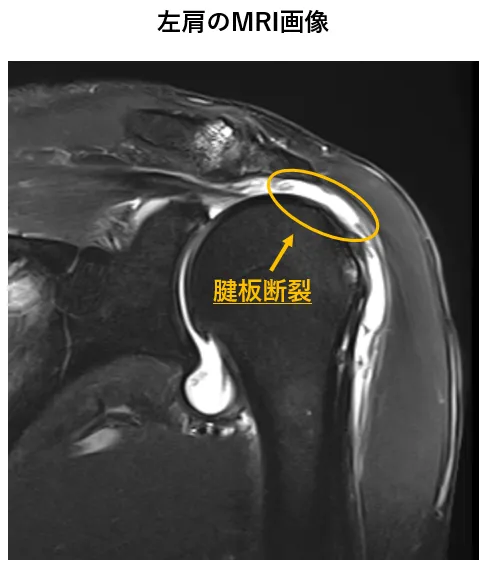

左腱板断裂

半年前、筋力トレーニング中に左肩に激しい痛みを感じ、近くのクリニックで腱板断裂と診断されました。様々な関節注射などの治療を受けましたが、効果はありませんでした。手術以外に治療法はないと考えていたところ、シンセルクリニックのホームページで再生医療を知り、受診を決意しました。再生医療の注射を受けたところ、1回目から驚くほどの効果があり、全く上がらなかった腕が痛みなく上がるようになりました。その後、計3回の注射を受け、さらに痛みが改善し、現在では問題なく肩を動かせる状態になっています。手術をせずに痛みが軽減し、再生医療を受けて本当に良かったと感じています。